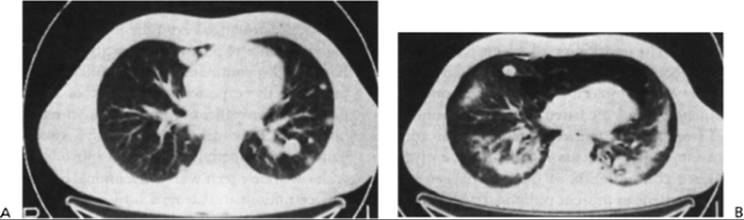

Clinical symptoms of bleomycin pulmonary injury include a nonproductive cough, dyspnea, and occasionally fever and pleuritic pain. Physical examination usually reveals minimal auscultatory evidence of pulmonary alveolar infiltrates, and initial chest films are often negative or may reveal an increase in interstitial markings, especially in the lower lobes, with a predilection for subpleural areas. Chest radiographs, when positive, reveal patchy reticulonodular infiltrates, which in later stages may coalesce to form areas of apparent consolidation. In occasional patients, the initial radiographic changes may be discrete nodules indistinguishable from metastatic tumor; central cavitation of nodules may be present146, 147 (Fig. 15.7). Gallium-67 lung scans or computed tomographic scans (Fig. 15.8) may show the presence of a diffuse lung lesion at a time of minimal abnormality on plain films of the chest; computed tomographic scans are much more sensitive than posteroanterior chest films in revealing the extent of pulmonary fibrosis. Radiologic findings do not differentiate bleomycin lung toxicity from other forms of interstitial lung disease,148 however, particularly Pneumocystis carinii pneumonia. Arterial oxygen desaturation and an abnormal carbon monoxide diffusion capacity are present in symptomatic patients with bleomycin toxicity as well as in patients with other forms of interstitial pulmonary disease. Thus, open lung biopsy is usually required to distinguish between the primary differential diagnostic alternatives, specifically a drug-induced pulmonary lesion, an infectious interstitial pneumonitis, and neoplastic pulmonary infiltration. The findings on histologic examination of human lung after bleomycin treatment closely resemble those previously described in the experimental animal and include necrosis of Type I alveolar cells, an acute inflammatory infiltrate in the alveoli, interstitial and intraalveolar edema, pulmonary hyaline membrane formation, and intraalveolar and, later in the course, interstitial fibrosis. In addition, squamous metaplasia of Type II alveolar lining cells has been described as a characteristic finding.149 In rare cases, a true hypersensitivity pneumonitis may develop, characterized by underlying eosinophilic pulmonary infiltrates and a prompt clinical response to corticosteroids.150

Figure 15.7 A: Typical interstitial pulmonary infiltrates, most obvious in left lung, observed during treatment of a patient with testicular carcinoma. B:Nodular variant of bleomycin pulmonary toxicity in a patient undergoing treatment for testicular cancer. Computed tomographic scan of chest showing a nodular density with central cavitation. On biopsy, the lesion was found to be composed of granulomas with associated interstitial pneumonitis. Appropriate stains and cultures did not reveal infectious agents. (From Talcott JA, Garnick MB, Stomper PC, et al. Cavitary lung nodules associated with combination chemotherapy containing bleomycin. J Urol 1987;138:619.)

Figure 15.8 Computed tomographic scans of the chest before (A) and after (B) treatment for testicular cancer. The multiple metastatic pulmonary nodules partially regressed with therapy, but the posttreatment film shows dense bilateral pulmonary fibrosis as well as a large left pneumothorax and pneumomediastinum. The patient died of bleomycin pulmonary toxicity shortly afterward.